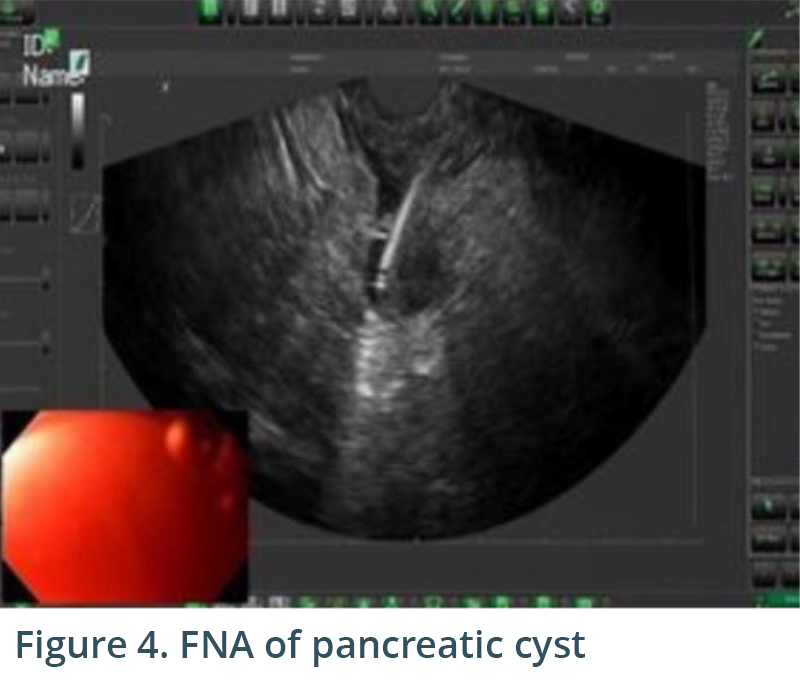

Endoscopic exam revealed gastritis (Fig 1) and duodenitis in duodenal bulb (Fig 2). Pancreatic parenchyma was without mass, and there was no dilation of main pancreatic duct. There was a cyst in head of pancreas measuring 4.7 x 2.5 mm and another in the body of pancreas measuring 5.1 x 4.3 mm. Both cysts were without mural nodule or associated mass and were too small for meaningful FNA. Tail of pancreas had a 14.6 x 12.9 mm cyst without mural nodule or mass status post FNA with 22G needle (Figs 3, 4) with aspiration of approximately 1.5-2 cc of viscous/straw colored fluid sent for analysis. Other etiologies of abdominal pain such as gallstones and biliary causes were ruled out during EUS (Figs 5,6).